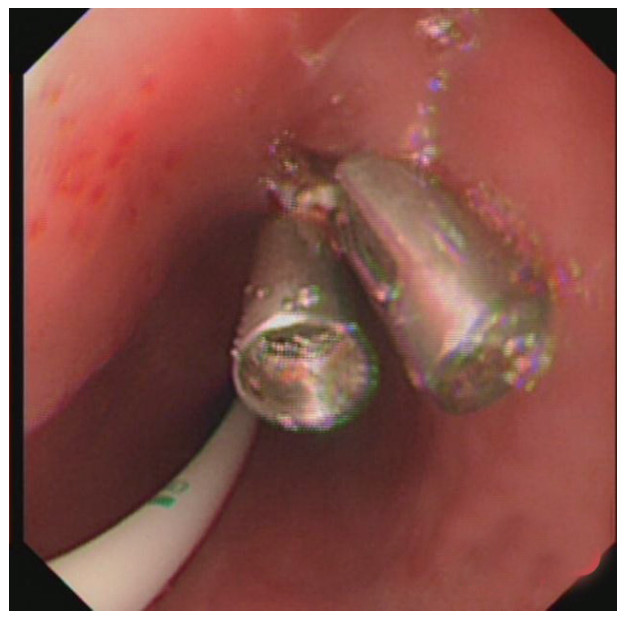

治疗经过:急诊予美罗培南0.5 g,1次/12 h抗感染,补液支持,心包引流等治疗措施,收住感染科后继续抗感染治疗,期间心包积液培养出白假丝酵母菌,加用氟康唑200 mg,1次/d, 口服,心包积液、左侧胸腔积液引流等措施,治疗10 d后复查胸部CT仍有中大量心包积液伴少许积气,纵隔积气;左侧少量胸腔积液,两肺叶间裂少许积液。对照前片(2020.10.26)心包积气及左侧胸前积液有增多,叶间裂积液新发,心包积液略有减少。右肺下叶感染,左肺下叶膨胀不全,较前右肺下叶感染有吸收,左肺下叶膨胀不全新发。考虑不能排除食管纵隔瘘,予口服碘海醇后胸部CT检查(图 3~6):约胸6椎体水平食管纵隔瘘,瘘口为相应水平食管壁右前方可能;胃镜(图 7):食道距门齿25 cm右后壁见一直径约1.0 cm凹陷,内有一小瘘口。胃镜下予钛夹2枚夹闭瘘口(图 8),同时植入空肠营养管。至此患者病情明确诊断食管心包瘘,患者经以上治疗后心包积液、胸腔积液逐渐减少,于11月13日拔除心包及胸腔引流管,因患者签字回当地就诊,予口服莫西沙星、氟康唑带药出院,出院后随访,患者未回当地医院治疗,仅在家中继续空肠营养管饲喂及口服抗菌药物治疗。

| 图 3 白色箭头所指为气管隆突下方纵隔内积气,红色箭头所指为食管 |